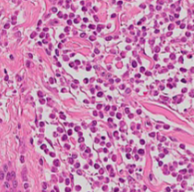

Visualization of tile classification results on a WSI from the CATCH dataset. The left panel (baseline) shows classification using non-contextual tile embeddings, whereas the right panel (TICON) displays classification with contextualized embeddings. TICON produces less noisy predictions and corrects many local misclassifications (green boxes). However, we also observe shared failure modes (orange box) where both methods misclassify a region. This suggests limitations in the underlying tile encoder's features. Indeed, the latter can miss some necessary information that even contextualization cannot retrieve.